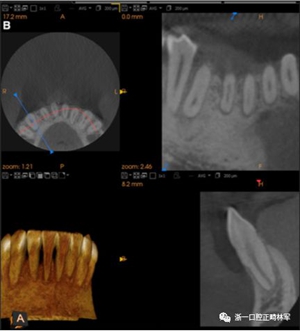

臨床檢查顯示固定保持器完好,弓絲沒有斷裂(圖13)。在下頜右側(cè)中切牙唇側(cè)和鄰近側(cè)切牙的舌側(cè)注意到有牙齦退縮。這些牙齒在退縮方向上存在顯著的扭矩差異。下頜的左側(cè)尖牙頰側(cè)錯(cuò)位,而右側(cè)尖牙舌側(cè)傾斜。三維射線照片證實(shí)了下頜右側(cè)尖牙面?zhèn)妊啦酃菃适?,右?cè)中切牙的喪失程度較輕。右側(cè)側(cè)切牙根也從舌側(cè)骨面上扭轉(zhuǎn)出來(圖14)。

圖14.三維立體圖像:A,面部和B,切牙根部的舌側(cè),剛?cè)〕龉潭ㄉ鄠?cè)保持器后。